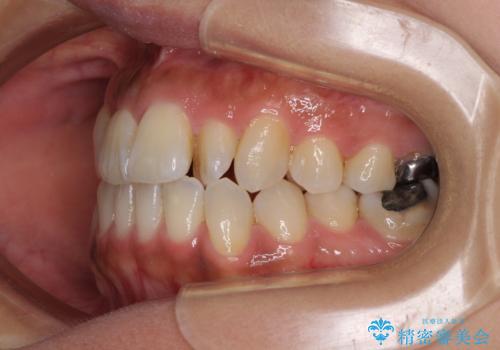

- 上の歯の歯並びを気にして来院された患者様です。

上顎骨の横幅が狭く、歯列が混み合っていたため、急速拡大装置により側方拡大し、咬み合わせと歯列を改善することとしました。

下顎は部分的に咬み合わせに問題があったため、部分的な装置を付けることとしました。